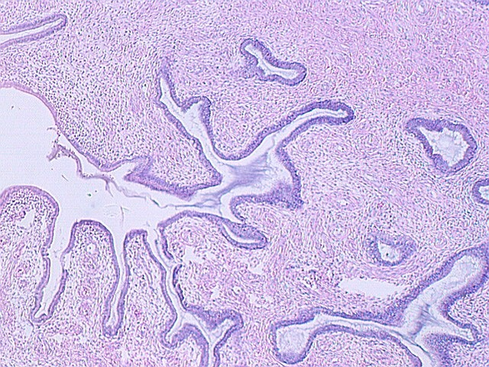

The uterus communicates with the outside world via a short canal called the cervix. The following photograph shows the uterus in the proliferative stage. The glands continue into the cervix in the left side of the photo.

The cervix continues and joins with the vagina. The cervix is lined by simple high columnar epithelium which consists of mucous cells. These are shown in the following views. In the lowest magnification, one can see bundles of smooth muscle in the wall (see below)